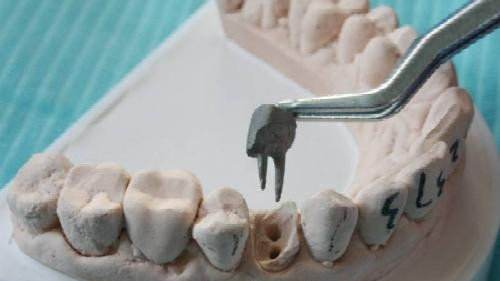

7、根管打桩:因牙体缺损过多,导致牙的强度(承受力量的性能)大幅度下降,不能很好地承受咀嚼力量。打桩的目的是增加牙根及牙冠的强度,增加患牙的稳固。

8、完成牙体修复:X线片显示根管充填完好,行暂时或永久牙体修复,带上牙冠,保护患牙。至此根管治疗才可算完成,同时根管治疗后还需复诊,一般周期可为3个月、半年、1年、2年或更长。